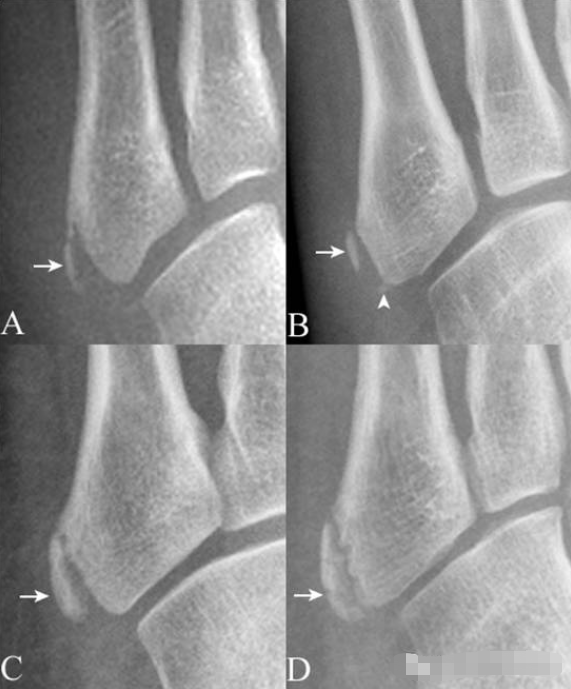

16.第5跖骨粗隆骨化中心:

第5跖骨粗隆骨化中心(箭),形态多样,A(女,10岁)为线样且不连续,B(男,13岁)为多发(箭与箭头),C(男,12岁)为边缘光整,D(男,11岁)为内缘粗糙伴裂隙。需与撕脱骨折鉴别,其与粗隆长轴近似平行,而撕脱骨折为腓骨短肌肌腱牵拉所致,骨折线多为横行。